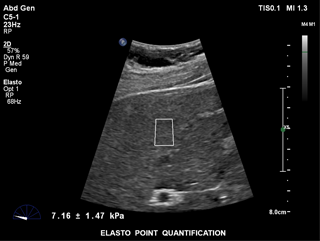

ElastPQ est une méthode d’évaluation de la rigidité hépatique facile d’utilisation permettant d’obtenir les valeurs sur une ROI prédéfinie. L’imagerie en temps réel servant de masque et guide, la ROI est positionnée sur la zone d’intérêt et les données relatives à la dureté des tissus (moyennes et écart interquartile, notamment) sont obtenues et affichées en quelques secondes. Plusieurs échantillons peuvent être enregistrés et un rapport sur les tissus hépatiques peut être généré à partir des résultats.